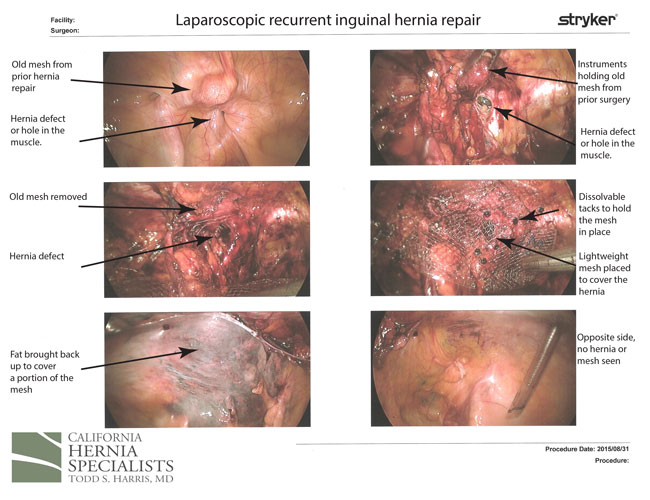

Thus, she presented to California Hernia Specialists for a second opinion. We ordered an ultrasound which showed a hernia still located in the left groin. Due to the fact that she had just undergone an open surgery, we offered her a laparoscopic hernia repair in the left groin. We were not sure what we would see at the time of surgery since the prior surgeon said he clearly did not find a femoral hernia.

At the time of our surgery, we saw the prior surgeons use of an older ‘plug’ type hernia mesh located in the ‘direct hernia’ space. However, we saw a very clear femoral hernia just below this direct hernia. To adequately repair the femoral hernia, we had to remove the prior plug, and cover the entire area with a laparoscopic mesh.

The patient did great and has not had a recurrent bulge since her surgery. The images below are from her surgery